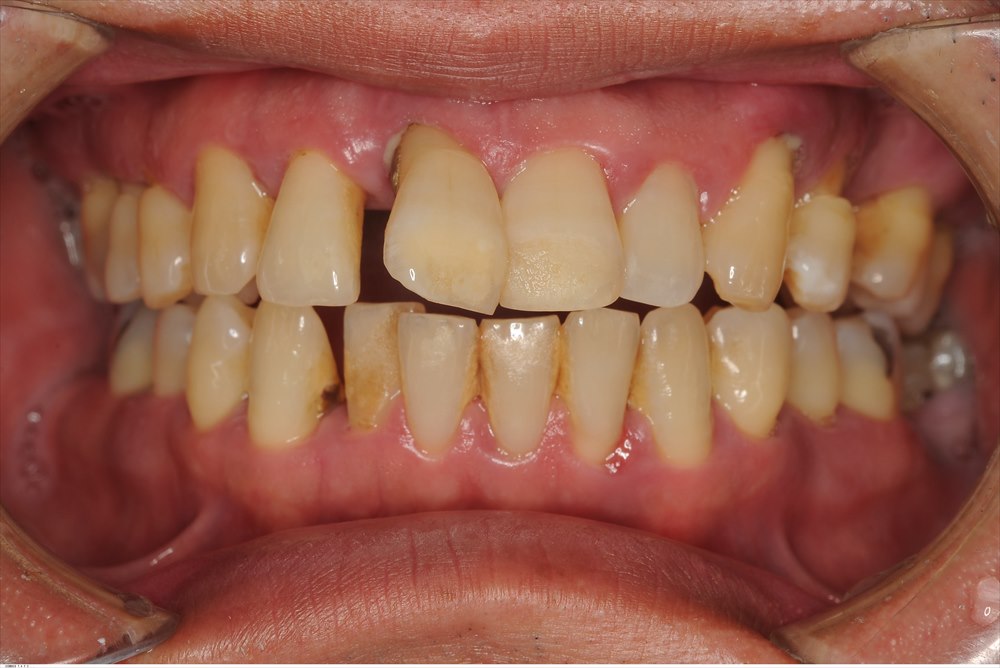

こちらが初診時の口腔内写真です。ほぼすべての歯茎から膿が出ていました。